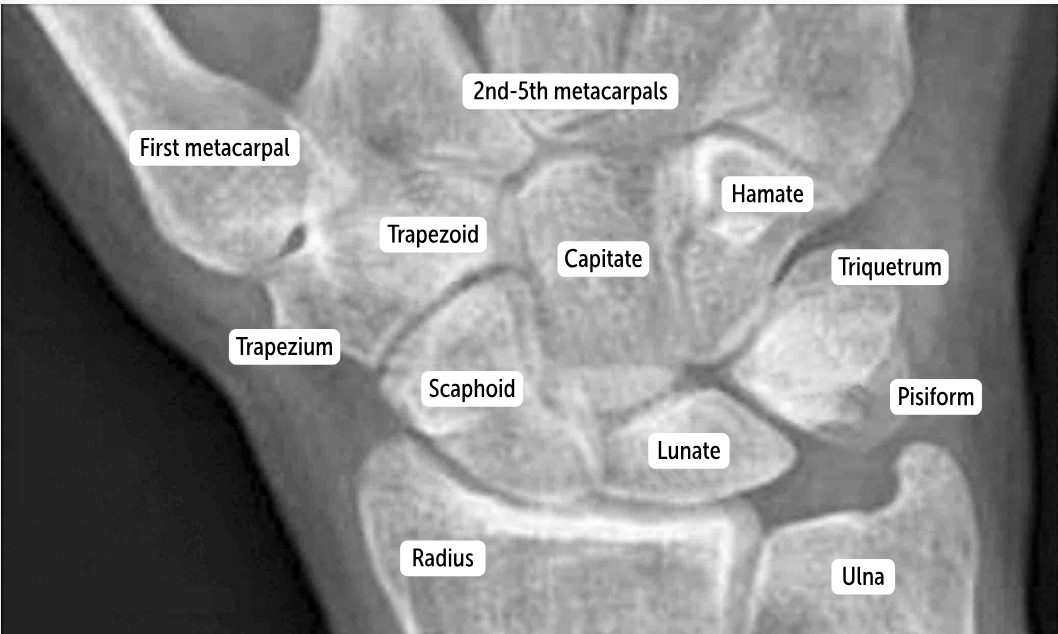

The most commonly fractured carpal bone by falling on an outstretched hand, which has a risk of avascular necrosis, is the __________.

Scaphoid bone

The most commonly dislocated bone after a fall on an outstretched hand is the ___________.

Lunate bone

Carpal bones by row:

So Long To Pinky, Here Comes The Thumb

Scaphoid, Lunate, Triquetrum, Pisiform, Hamate, Capitate, Trapezoid, Trapezium

Scaphoid

Lunate

Triquetrum

Pisiform

Hamate

Capitate

Trapezoid

Trapezium

The two distinct rows articulate with each other at the __________. It’s a plane (simple sliding) joint that acts to amplify all the other wrist actions.

midcarpal joint

Which carpal bones articulate with the metacarpal bones?

The bones of the distal row (hamate, capitate, trapezoid, and trapezium) articulate with the metacarpal bones.